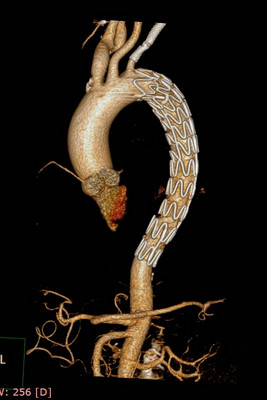

充分的术前评估及准备,确保了手术的顺利进行。术中王兵教授亲自主刀,崔文军副主任及王颖、司江涛主治医师作为助手,经股动脉小切口,先于左侧锁骨下动脉狭窄处准确定位后置入球扩支架1枚,再次造影明确溃疡位置后,将主动脉带膜支架顺利输送到位,并成功释放,完全覆盖病变主动脉,复查造影效果满意(图3)。术后患者即清醒,安全返回病房,测量双上肢血压无差别,双下肢温度、颜色正常,感觉及运动均无异常,即挽救了患者生命,也成功避免了截瘫的发生,大家悬着的心都放了下来。术后施敏护士长带领的护理团队,娴熟而全面的护理确保患者平稳度过围手术期,术后10天复查CTA:左侧锁骨下动脉及主动脉支架均位置良好,形态满意。目前李大娘已顺利康复出院。

图3:术中支架释放后造影 图4:术后10天复查CTA